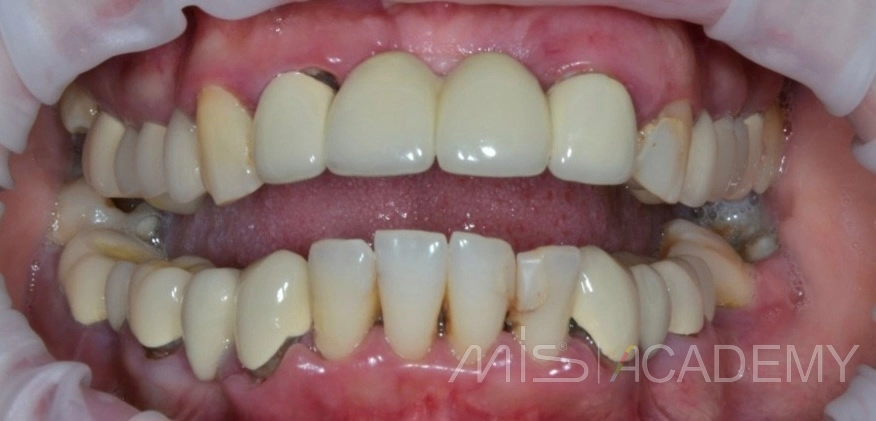

Клинический случай НКР верх фронт и последующие АО4 верх-низ.